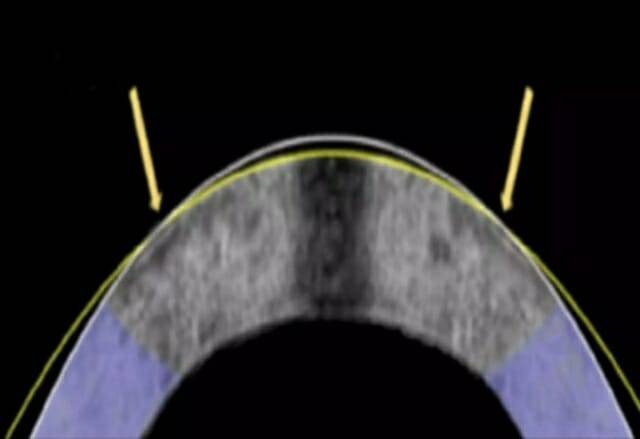

연구진은 각막의 구성 성분을 이용해 어떤 조직도 잘라내지 않고 각막의 형태를 바꾸는 방식을 제안했다. 주로 콜라겐으로 이루어진 각막은 전하를 띤 분자와 단백질의 배열 덕분에 형태를 유지한다. 연구진은 특별히 설계된 백금 콘택트렌즈에 저전류를 흘려 보내 조직의 pH를 변화시켜 각막 조직의 산성도를 높여 모양을 바꿀 수 있다는 것을 발견했다.

이후 전류가 멈추면 pH가 정상으로 돌아오면서 각막은 다시 단단해지고 원래 모양을 유지하게 된다. 이 과정은 1분 정도 소요되며, 조직을 절개하거나 제거할 필요가 없다. 이 방법은 실험 샘플에서 구조적 손상이 나타나지 않았고 세포 생존율도 유지됐다. 연구진은 EMR이 라식 수술을 대체할 수 있을 것으로 기대한다.

연구진은 토끼 안구 12개에 EMR 기법을 적용해 테스트 해 그 중 10개의 안구를 변형시켜 근시 교정 효과가 나타난 것을 확인했다. 전류에 단시간 노출된 후, 각막은 렌즈에 내장된 모양에 맞춰져 모양이 바뀌었고 레이저나 외상 없이도 성공적인 각막 교정이 확인됐다.